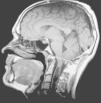

Los epónimos malformación de Chiari y Arnold-Chiari han sido utilizados como sinónimos para definir a una serie de malformaciones que se caracterizan por la existencia de una ectopia de las amígdalas del cerebelo que se sitúan por debajo del foramen mágnum. De una forma casi generalizada, y por un sentido de justicia histórica, el epónimo malformación de Arnold-Chiari ha sido sustituido por el de malformación de Chiari. Clásicamente se han diferenciado cuatro tipos de malformaciones de Chiari, en función de las anomalías asociadas, aunque la más frecuente es la malformación de Chiari tipo I (MC-I), para la que se exige que las amígdalas del cerebelo se sitúen al menos 3mm por debajo del foramen mágnum (fig. 1)1. Sin embargo, en el momento actual existen todavía importantes controversias clínicas, etiopatogénicas y terapéuticas relacionadas con esta malformación.